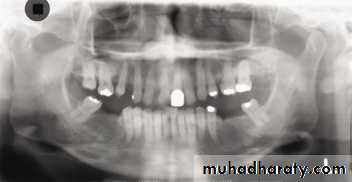

In a good panoramic radiograph:

The mandible is “U” shaped.The condyles are positioned about equal distance from the inside edges of the image and 1⁄3 of the way down from the top edge of the image.

The occlusal plane exhibits a slight curve or “smile line,” upwards.

The roots of the maxillary and mandibular anterior teeth are readily visible with minimal distortion.

Magnification is equal on both sides of the midline.